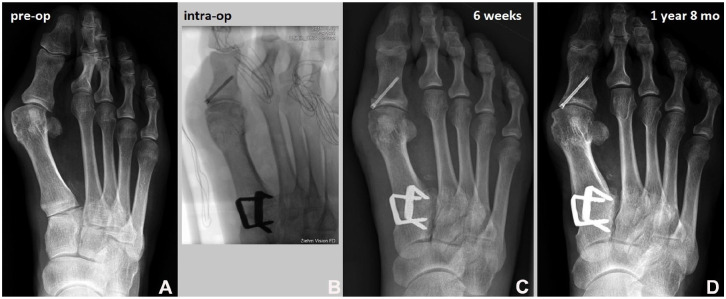

Methods: A total of 60 cases undergoing Lapidus arthrodesis between June 2018 and June 2022 were analyzed with a median follow-up of 37 months (range: 15-64 months). All cases were treated using two nitinol staples (BME EliteTM; DePuy Synthes) for TMT1 fusion. Among these, 38 cases involved additional foot procedures, while 22 cases had isolated TMT1 fusion. Data were collected from medical records, radiographs, and a telephone survey. The hallux valgus angle (HVA) and intermetatarsal angle (IMA) were measured preoperatively and postoperatively on weightbearing dorsoplantar radiographs. Functional outcomes were assessed using the Foot and Ankle Ability Measure-Activities of Daily Living (FAAM-ADL) subscale, and patient satisfaction was evaluated using a 4-point Likert scale.

Results: The TMT1 fusion rate was 96.7% (58/60). The reoperation rate-including hardware removal, revision surgery for recurrence, and nonunion-was 16.7%. The staple breakage rate was 3.3%. The IMA improved from 15.8 to 8.9 degrees (P < .001), and the HVA improved from 37.5 to 17.3 degrees (P < .001). The average FAAM-ADL score was 81.7 out of 84, with 90% of patients reporting being very satisfied or satisfied.